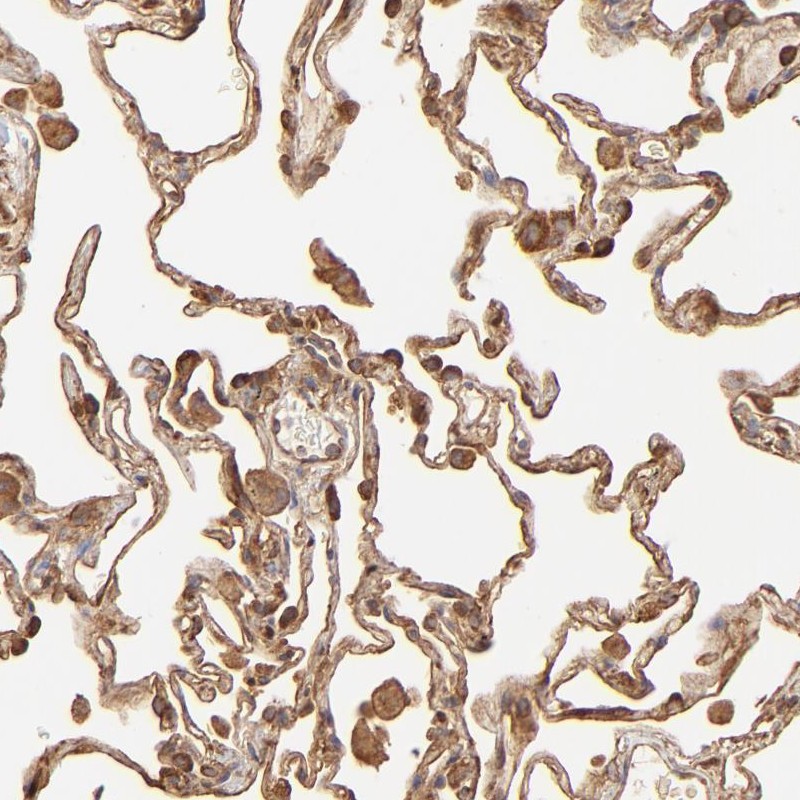

Immunohistochemical staining of human lung shows cytoplasmic and membranous positivity in pneumocytes.